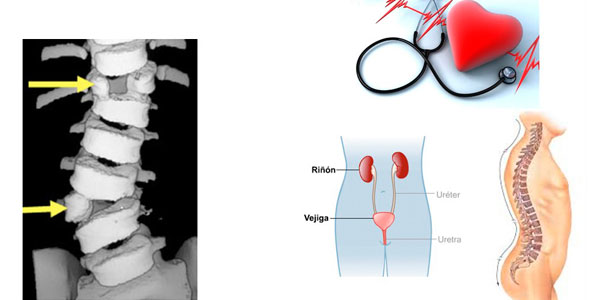

Al tener un diagnostico de escoliosis congenita debe descartarse otras malformaciones en otros organos y/o sistemas:

Corazón.

Genito-urinarias.

Anomalias intraespinales.

Es necesario evaluar con detalle al niño y solicitar estudios de imágenes que nos puede mostrar la estructura de la columna en forma completa.